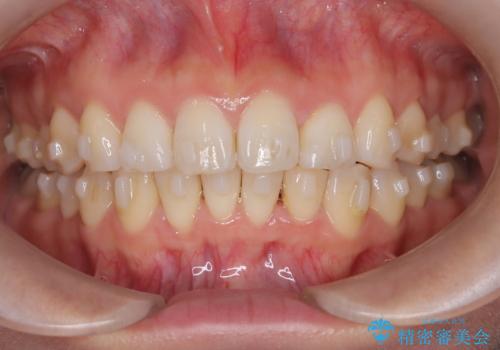

- 「歯のガタつきが気になる」「前歯の真ん中がずれている」との主訴で来院されました。診察の結果、上下の歯列に中等度の叢生(凸凹)があり、特に前歯の位置のずれ(正中の偏位)が目立つ状態でした。見た目だけでなく、かみ合わせにも影響を与える可能性があるため、全体的なバランスの改善が必要と診断しました。

治療はインビザラインを使用し、1~2週間ごとに新しいマウスピースに交換しながら段階的に歯を移動させていきました。特に上下の正中が揃うよう、奥歯や前歯の位置関係に注意を払いながら細かく設計を調整。途中の確認でも、左右のバランスが取れてきたことをご本人も実感されていました。

治療期間は約1年半で、ガタついていた歯列はきれいに整い、上下の前歯の真ん中もぴったりと揃えることができました。透明なマウスピースのため周囲に気づかれず治療が進み、快適に続けられたとの感想もいただいています。